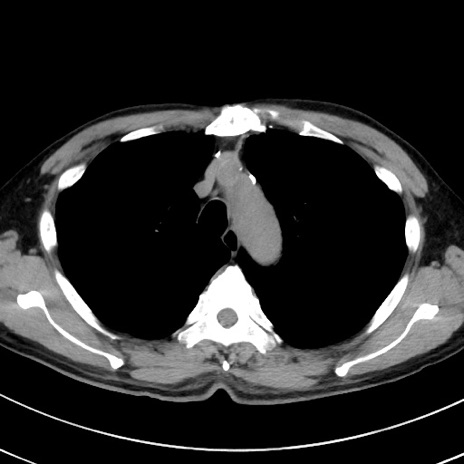

症例38(横断像)

【症例】70歳代 男性

【主訴】腹痛・嘔吐

【現病歴】昨晩より、嘔吐・腹痛あり。今朝になっても嘔吐あり。来院。

【既往歴】心臓バイパス手術、開腹胆摘、腸閉塞

【身体所見】BP 107/71mmHg、HR 116/min、腹部:平坦、軟、下腹部に軽度圧痛あり。反跳痛なし。

【データ】WBC 15100、CRP 0.32

冠状断像